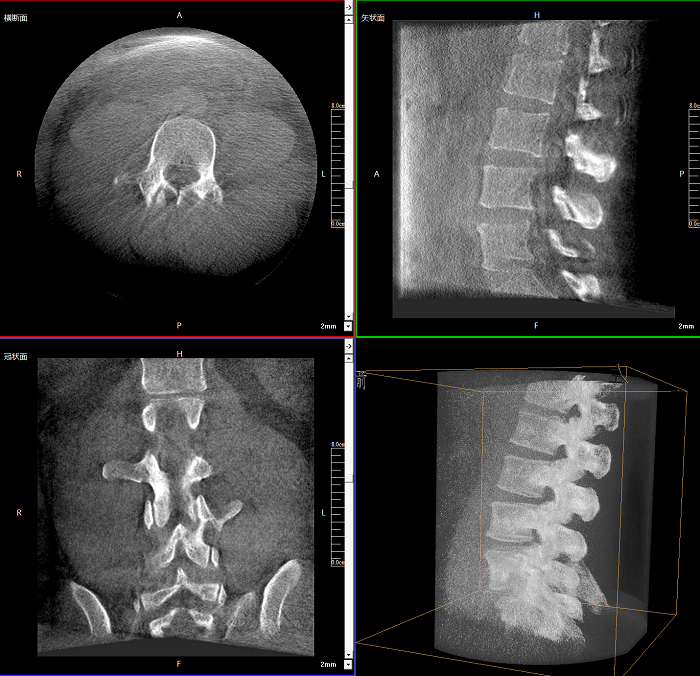

該設(shè)備可進(jìn)行快速的術(shù)中三維掃描,生成類CT斷層圖像和立體3D圖像,保障植入物置入效果。廣泛適用于骨科、脊柱外科、矯形外科、創(chuàng)傷骨科等其他領(lǐng)域。

●極速成像僅需8秒,從數(shù)據(jù)采集結(jié)束到完成三維重建斷層影像